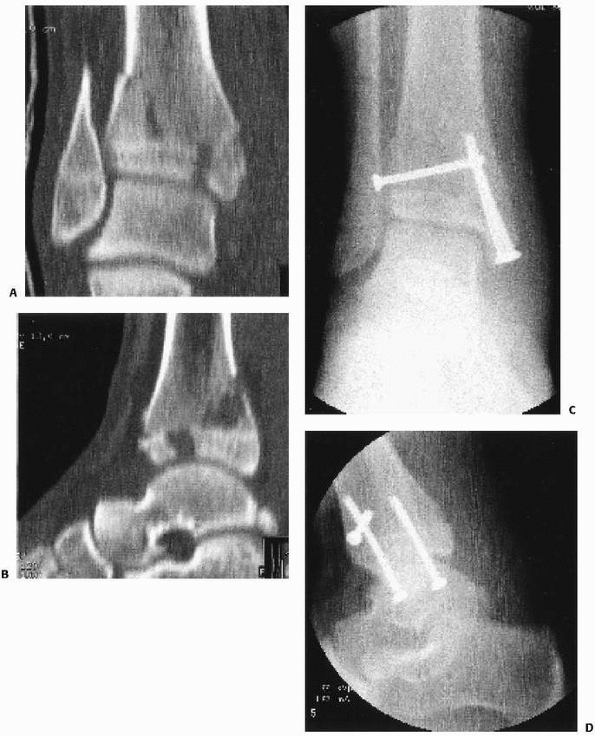

![]() |

FIGURE 26-48 Preoperative (A,B) and postoperative (C,D) anterior posterior and lateral views of an adolescent pilon fracture.

fracture of the “tibial plafond with articular and physeal involvement,

variable talar and fibular involvement, variable comminution, and

greater than 5 mm of displacement” (Fig. 26-12).105 Based upon a small number of cases, Letts et al.105

developed a three part classification system. Type 1 fractures have

minimal comminution and no physeal displacement. Type 2 fractures have

marked comminution and less than 5 mm of physeal displacement. Type 3

fractures have marked comminution and more than 5 mm of physeal

displacement.